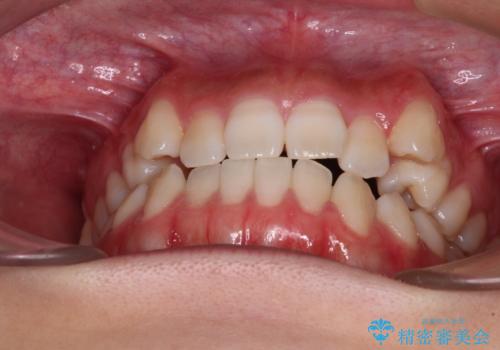

【モニター】上顎が狭い 急速拡大装置を用いたデコボコの解消

- 前歯の開咬と、上顎前歯の八重歯やデコボコを気にして来院された患者様です。

上顎歯列が狭窄していたため、急速拡大装置により上顎骨を側方に拡大し、その後ワイヤー装置にて矯正治療を行うこととしました。